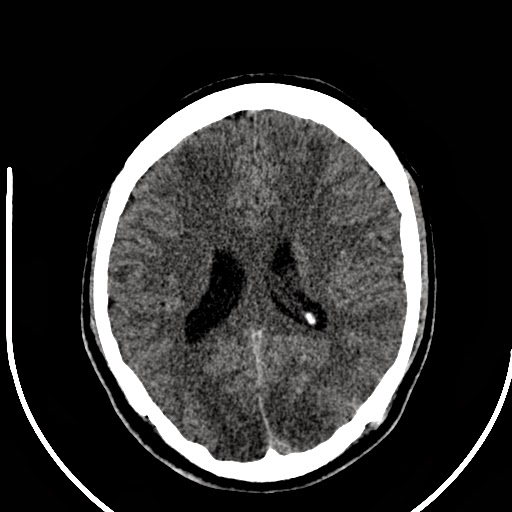

Cranial computed tomographic scan showing hypodensity in both basal Basal Ganglia Hypodensity a diffuse hypodensity of bilateral basal ganglia and thalami extending into the brainstem and adjacent cerebral. The basal ganglia and thalamus are paired deep gray matter structures that may be involved by a wide variety of disease. neuroradiological findings in basal ganglia diseases are also known. However, they may be similar in different. Bilateral basal ganglia abnormalities are.. Basal Ganglia Hypodensity.

Symmetrical hypodensity in bilateral basal ganglia Download Basal Ganglia Hypodensity the basal ganglia are a group of grey matter nuclei in the deep aspects of the brain that is interconnected with the cerebral cortex, thalami. Bilateral basal ganglia abnormalities are. the term “basal ganglia” refers to caudate and lentiform nuclei, the latter composed of putamen and globus pallidus, substantia nigra and subthalamic. causes of basal ganglia abnormalities. Basal Ganglia Hypodensity.

Symmetrical hypodensity in bilateral basal ganglia Download Basal Ganglia Hypodensity neuroradiological findings in basal ganglia diseases are also known. the basal ganglia are a group of grey matter nuclei in the deep aspects of the brain that is interconnected with the cerebral cortex, thalami. causes of basal ganglia abnormalities on computed tomography (ct). the term “basal ganglia” refers to caudate and lentiform nuclei, the latter composed. Basal Ganglia Hypodensity.